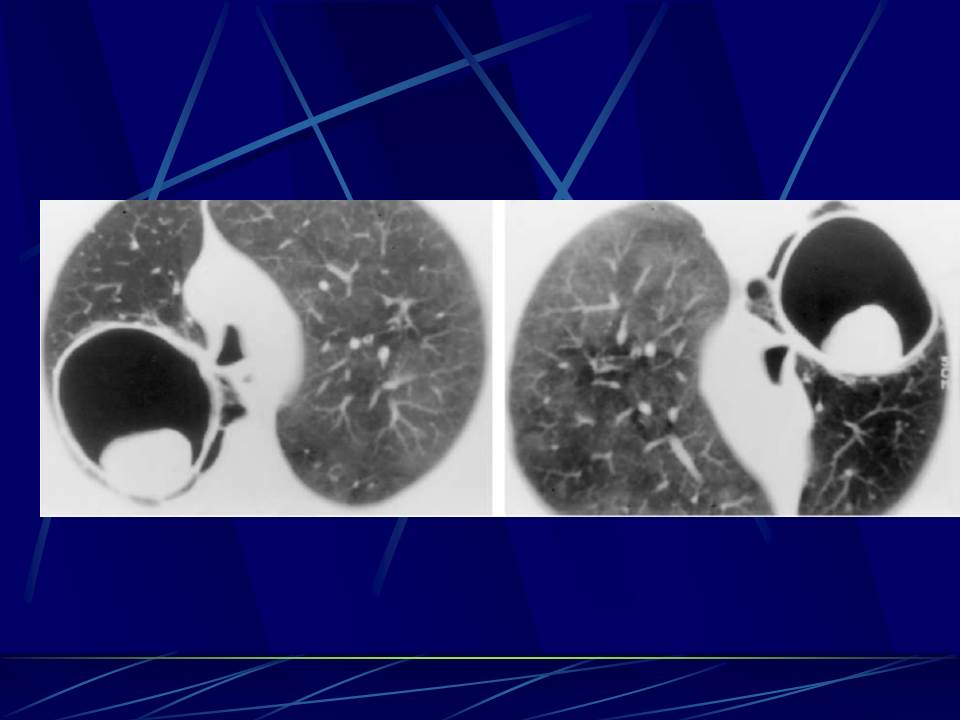

肺部真菌感染影像学分析